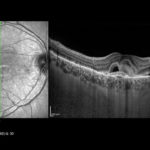

Misura degli spessori retinico e coroideale con OCT-EDI (Enhanced Depth Imaging)